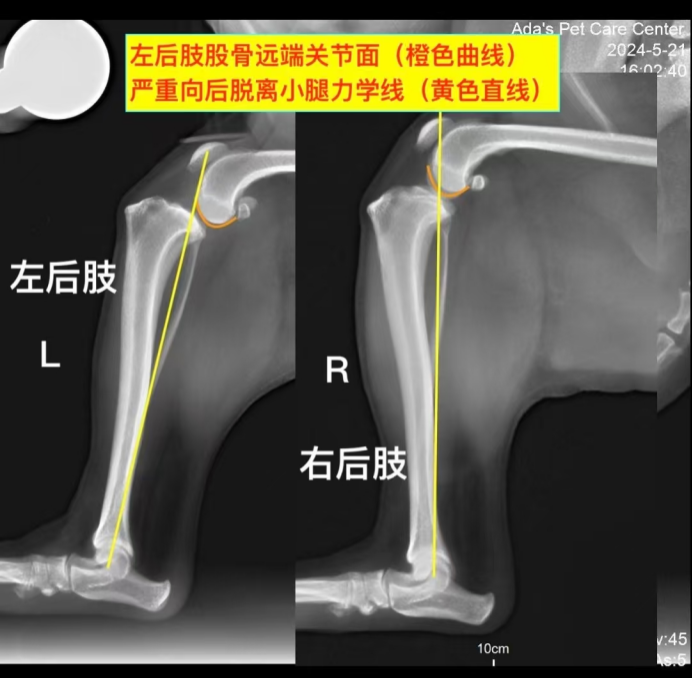

Due to the pain, further examination could not be conducted while the dog was awake, so sedation was administered. After sedation, a detailed check revealed a positive result for the tibial compression test, which clearly indicated a ruptured cranial cruciate ligament. X-ray imaging of the knee joint under load showed a subluxation of the femur and tibia. The diagnosis of a ruptured cranial cruciate ligament in the left hind leg was confirmed.